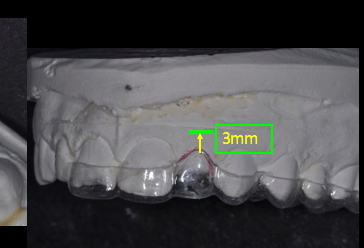

Implant depth is crucial for adequate “running room” and emergence profile. Ideally, the implant should be placed 3 mm apical to the gingival extent of the proposed restoration. Placing implants too shallow creates emergence contour limitations that create unesthetic gingival scallops. If the implant is placed too deeply, the tissue support and papilla formation may be compromised.

Tarnow has shown that if the distance of the implant platform and gingival tissue is greater than 5.0 mm, the interproximal papilla will be created less than 50% of the time. These surgical guides provide an unobtrusive visualization of the restoration margin and the implant platform at the time of placement.